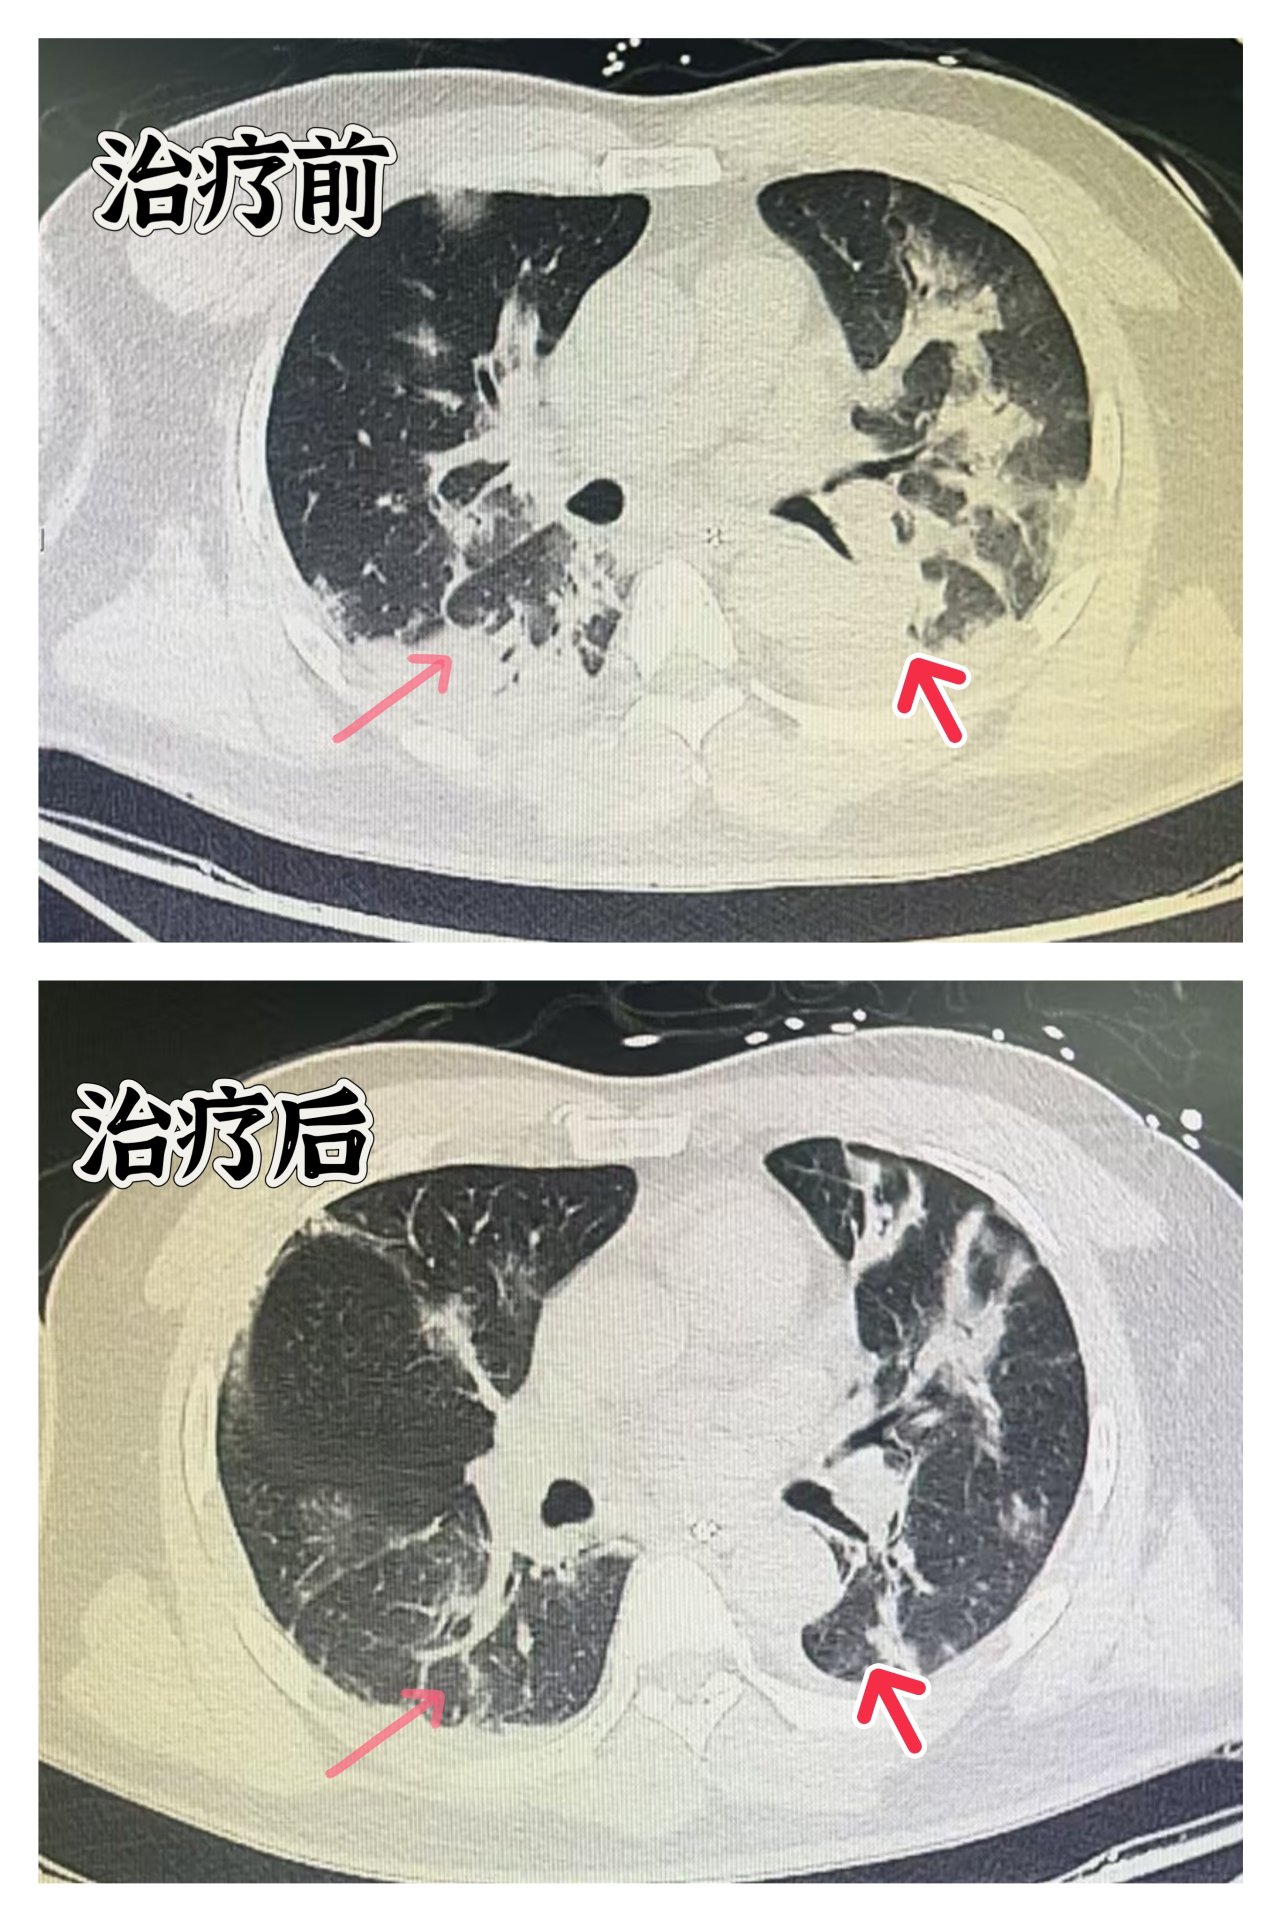

检测结果显示流感病毒抗原呈阳性,确诊为甲型流感病毒感染并发重症肺炎。影像学检查显示,患者的肺部已经出现“白肺”现象。随着病情的迅速恶化,患者出现了呼吸衰竭和循环衰竭的症状。

在重症医学中心ECMO团队的全力救治下,通过5天左右的ECMO心肺支持治疗,患者的肺部病变有了明显好转,目前正在康复中。